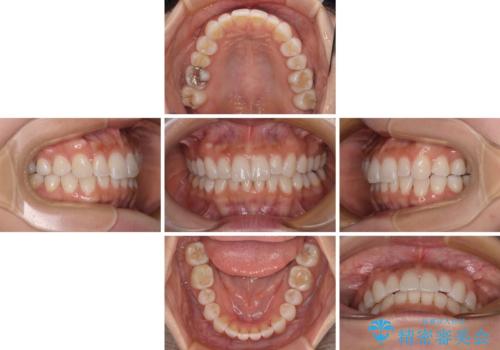

【モニター】前歯のデコボコと小さい前歯 インビザライン矯正とオールセラミッククラウン補綴治療

- 1年10ヶ月

上下前歯の歯列不正はインビザラインにより整え、その後に、矮小歯の前歯をオーダーメイドタイプのオールセラミッククラウンにて補綴治療することとしました。

インビザライン矯正の場合、矮小歯を矯正治療後にセラミックとするかどうかを矯正治療開始前に決める必要があるため、悩んでしまう方が多いです。

セラミッククラウンにて大きさを変更することを前提に矯正治療を開始したため、大変満足のいく仕上がりとなりました。